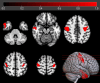

Results: sALS patients showed significant relative hypometabolism in bilateral fronto-temporo-occipital cortex and right insula as compared with FUS-ALS. After adjusting for age, the relative hypometabolism remained in the bilateral precentral gyrus and in the right middle and inferior temporal gyrus. As compared with HC, FUS patients displayed a significant relative hypermetabolism in the pontobulbar region and right cerebellar tonsil, dentate nucleus, and uvula, while sALS showed relative hypometabolism in bilateral frontal and occipital cortices and in left temporal and parietal regions.

Interpretation: Patients with FUS-ALS show relative preservation of motor cortex metabolism compared with those with sALS, possibly reflecting the prevalence of lower motor neuron impairment in their phenotype. Prospective studies are necessary to investigate the possible role of 2-[18F]FDG-PET as a biomarker to track disease spreading in clinical trials. ANN NEUROL 2025;97:1134-1143.